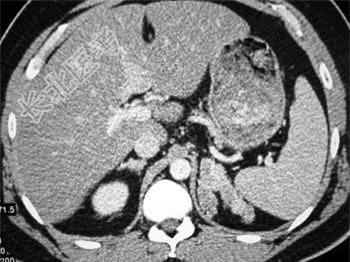

- 单项选择题男性,27岁, 侏儒,因脱水曾在数家医院住过院, 结合所示图像,最可能的诊断是 ( )

A、先天性肾上腺增生肥大

B、库欣综合征

C、肾上腺癌

D、腺瘤状增生肥大

E、嗜铬细胞瘤